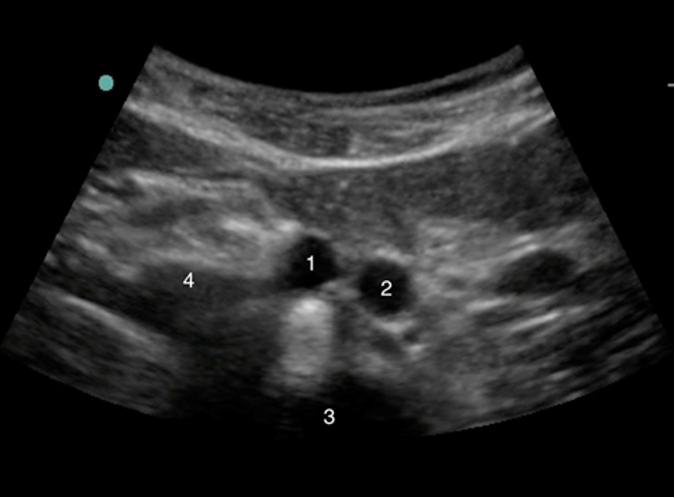

Aorta Bifurcation - Angle Below Umbilicus Image

1. Right Common Iliac Artery

2. Left Common Iliac Artery

3. Spine

4. Inferior Vena Cava (IVC)